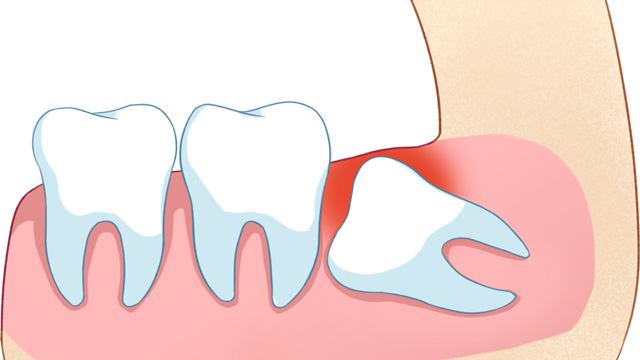

01智齿挤压邻牙,导致牙齿拥挤/移位

这是最常见的拔除原因。正畸的核心需求之一一般是“排齐拥挤牙齿”,而智齿作为口腔中最后萌出的牙齿(通常在20岁左右萌出),由于生长位置特殊、空间有限,很可能会持续挤压旁边的第二磨牙,导致第二磨牙倾斜、移位,进而引发整个牙列拥挤。

如果不拔除这颗“肇事智齿”,即使通过正畸排齐了牙齿,后期也会因为智齿的持续挤压,导致牙齿再次拥挤、反弹。

02智齿阻挡正畸牙齿移动

正畸治疗中,医生会根据诊疗方案,让牙齿沿着预设轨迹移动(比如前牙内收、后牙调整咬合等)。比如需要内收前牙改善凸嘴时,智齿的存在会“顶住”后牙,导致牙齿无法顺利移动到理想位置。这种情况,可能需要拔除智齿来为排齐牙齿提供必要的空间。